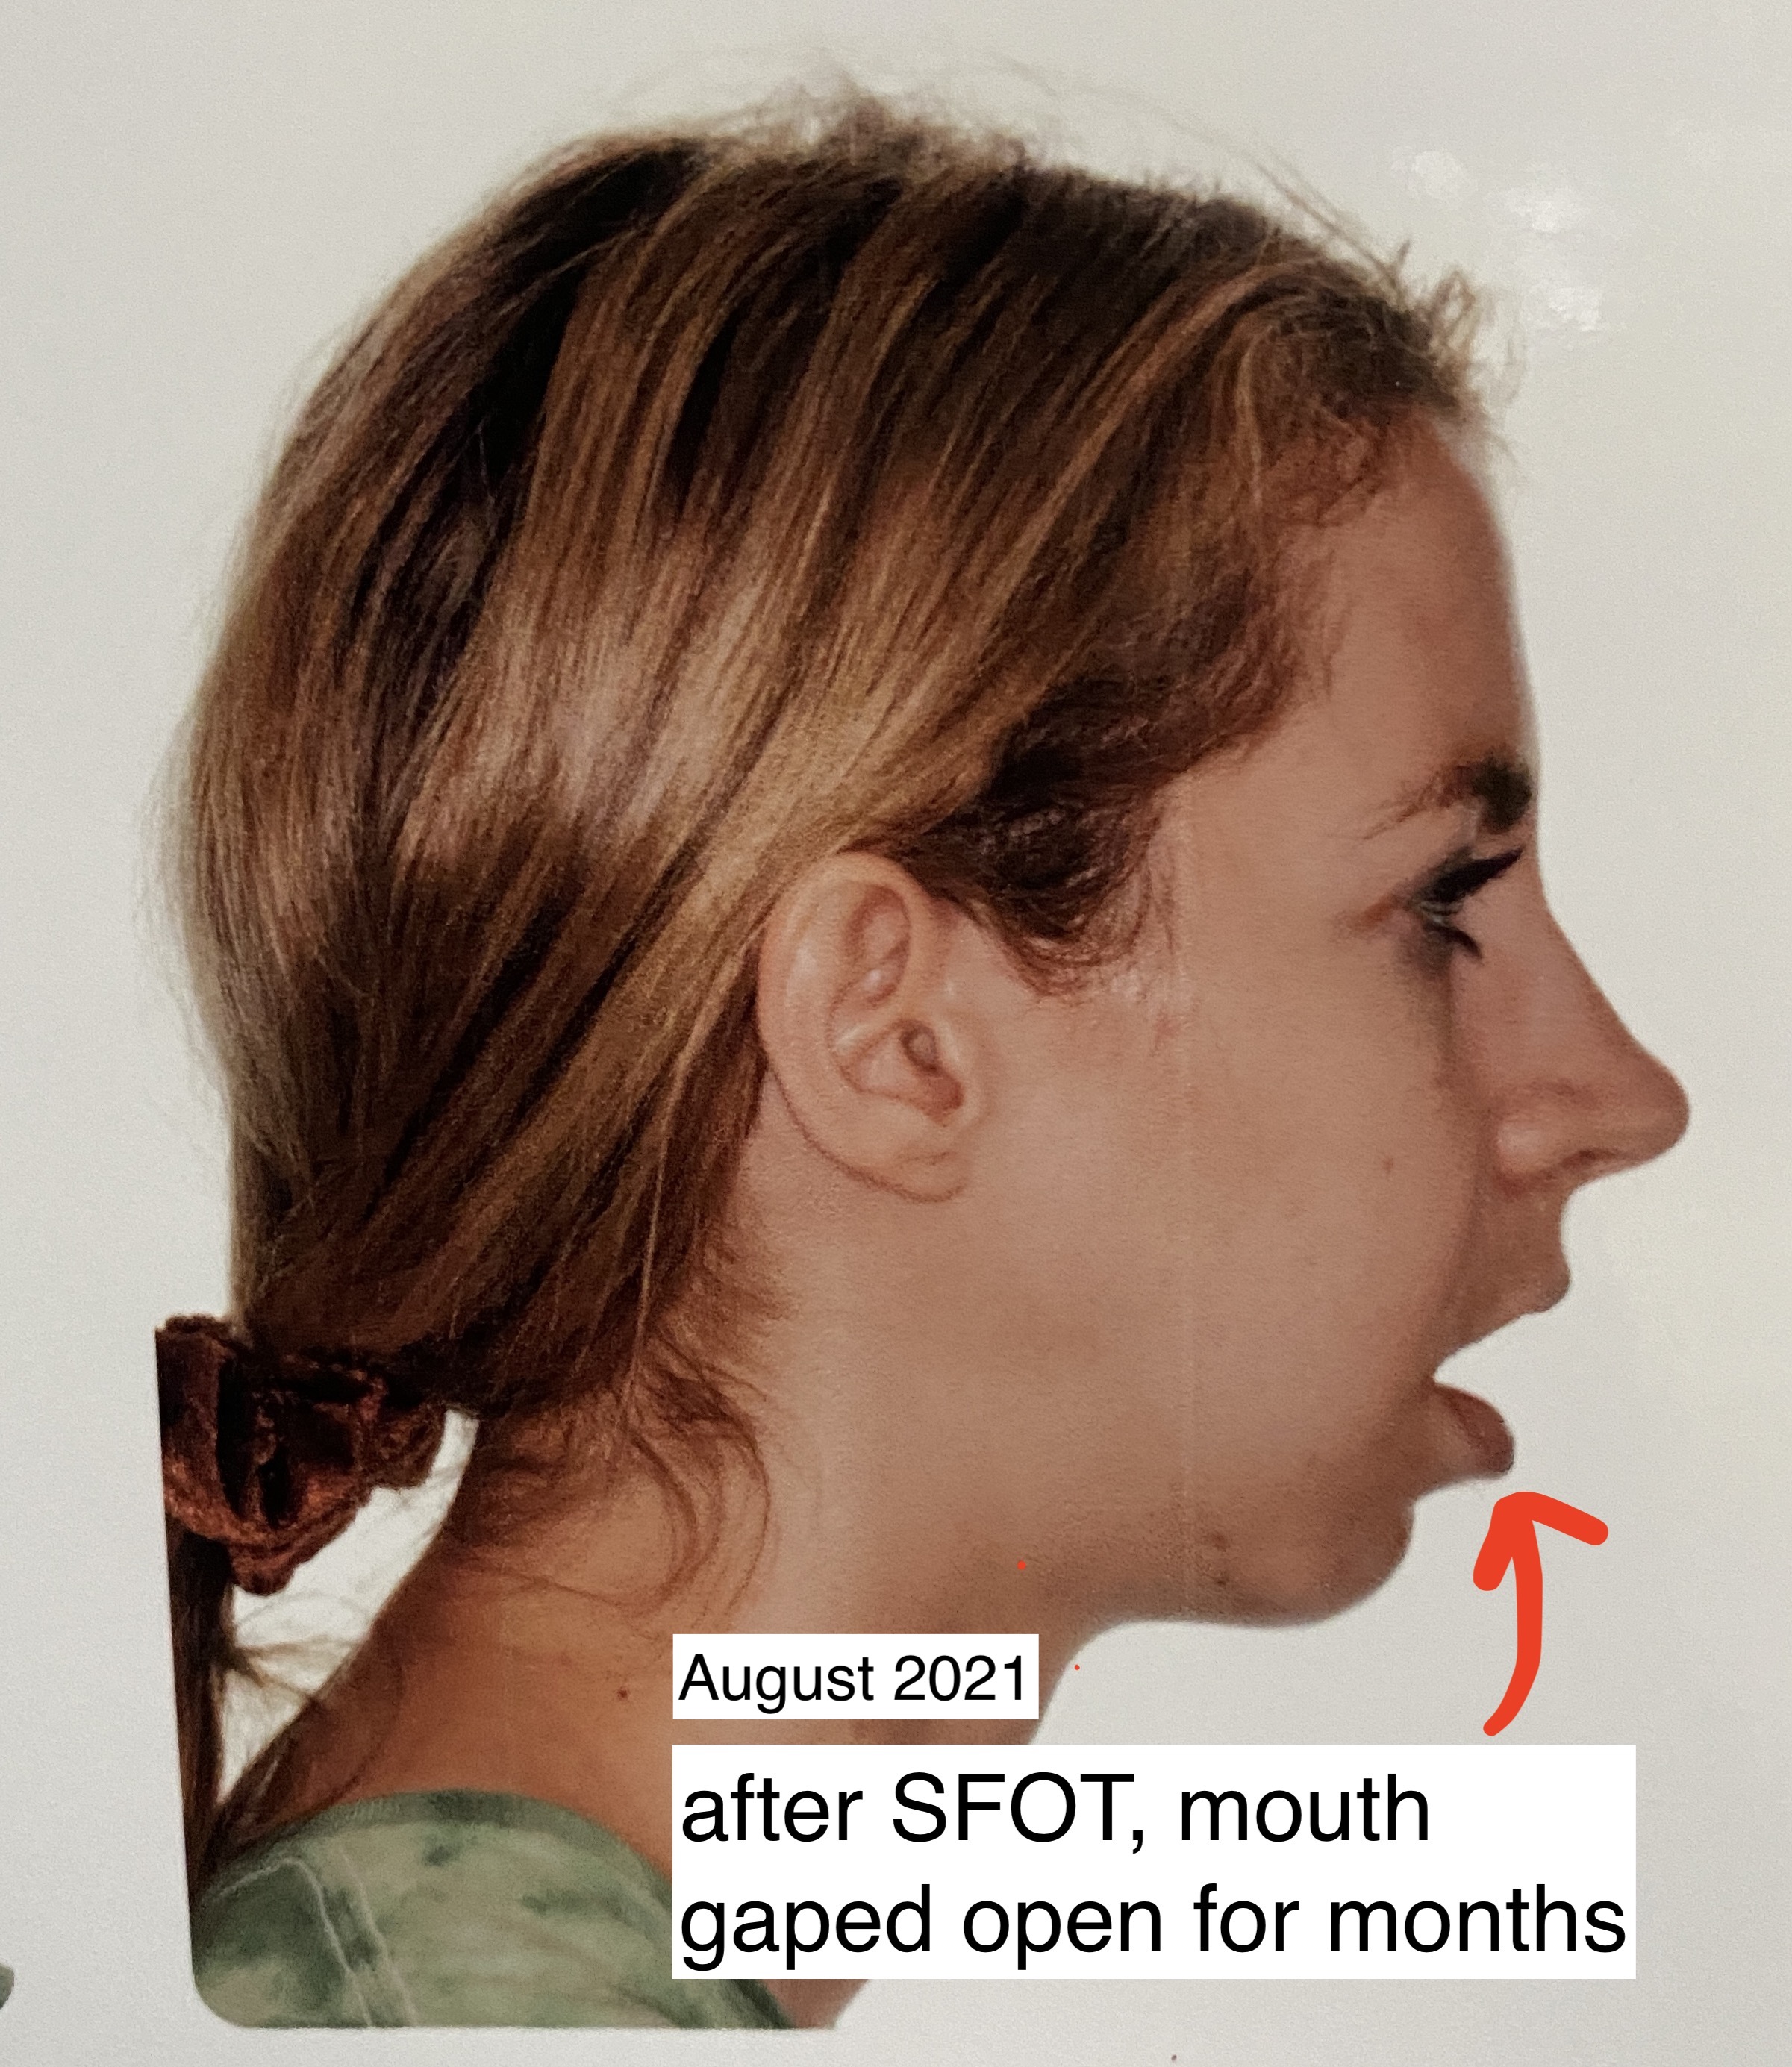

- Lips are closed: It is HEALTHY to breathe through the nose and to have your lips closed. Those with ICR are unable to do this without muscle strain, which encourages mouth breathing. Mouth breathing causes all. kinds. of. problems. You can read more about them here if you are interested: https://www.endur.com/blogs/blog/8-scary-consequences-of-mouth-breathing

I hope this gets better, and I imagine my soft tissue is needing to settle around for a little bit as well. My soft tissue had another change May 2021 from my SFOT surgery and my lips had to have a few months to settle in with the new bite, I imagine the back of my throat could be the same?